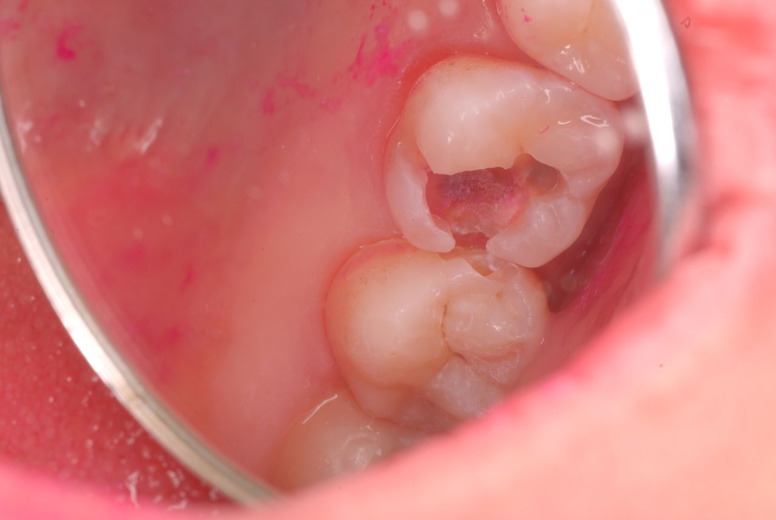

入れ歯の話から入りました。色々不満で注文があるようです。でも話が一段落して口腔内を調べると殆どの歯が重症で抜けそうな歯だらけなのです。

何故歯が悪くなるのか、歯周病で抜けるのか分からなければ何を入れても歯は悪くなり抜けていくのです。

病気を治しましょう。それから差し歯や入れ歯を入れましょう!物を入れれば入れるほど、磨き方や掃除の仕方が上手にならなければ、すぐ抜けてくるのです。